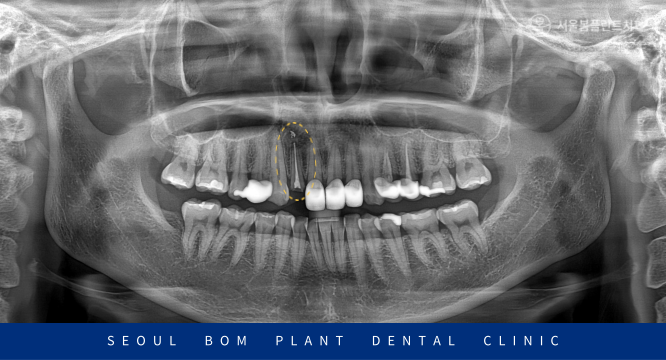

방이동치과 서울봄플란트치과에서는

눈에 보이지 않는 곳까지 확인하고

정밀한 검사를 위해

파노라마 사진을 촬영해 보았는데요.

다행히 기존 신경치료가 뿌리 끝까지

잘 되어 있었으며,

뿌리 끝 염증이나 통증 또한 없으셨습니다.

대개 이런 경우 의료진에 따라

발치를 해야 한다고 보는 경우가 많지만

환자분께서는 40대 초반의 젊은 나이셨습니다.

한 번 더 치아를 살려 사용하는 방법으로

치료를 진행하기로 계획을 수립하였습니다.